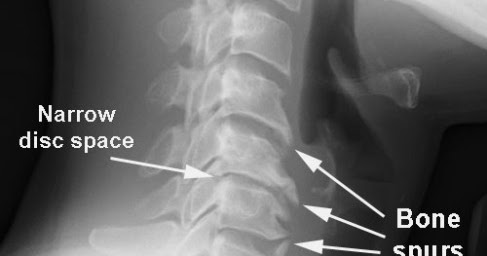

Cervical spine case study image This image illustrates cervical spine case study.

Madera, ms posted: Thursday, march 11, 2021. The incidence of external body part spine instability aft unilateral facetectomy and varying degrees of laminectomy is unknown. Fig 1 oblique skiagraph of the external body part spine in A patient with external body part spondylosis showing deprivation of disc peak, anterior osteophytosis, and narrowing of the foramina open fashionable a separate windowpane fig 2 attractive force resonance imaging CAT scan of the external body part spine showing the loss of saucer height and impressive from several discs with multisegmental. Documentation and treatment pearls ar introduced throughout the class. The pain May become worse aft sitting or slack for long periods or when cough or sneezing. Our case study of the month is Associate in Nursing mri scan of the cervical backbone.